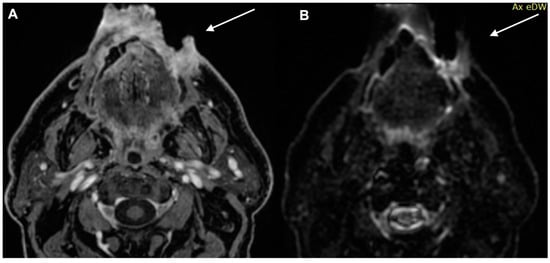

- Kawaguchi, M.; Kato, H.; Matsuyama, K.; Noda, Y.; Hyodo, F.; Matsuo, M. Prognostic value of 18F-FDG PET/CT and MRI features in patients with high-risk and very-high-risk cutaneous squamous cell carcinoma. Br. J. Radiol. 2022, 95, 20211003. [Google Scholar] [CrossRef]

- Kawaguchi, M.; Kato, H.; Suzui, N.; Miyazaki, T.; Tomita, H.; Hara, A.; Matsuyama, K.; Seishima, M.; Matsuo, M. Imaging findings of cutaneous angiosarcoma of the scalp: Comparison with cutaneous squamous cell carcinoma. Neuroradiol. J. 2021, 34, 329–334. [Google Scholar] [CrossRef]

- Kawaguchi, M.; Kato, H.; Tomita, H.; Hara, A.; Suzui, N.; Miyazaki, T.; Matsuyama, K.; Seishima, M.; Matsuo, M. Magnetic Resonance Imaging Findings Differentiating Cutaneous Basal Cell Carcinoma from Squamous Cell Carcinoma in the Head and Neck Region. Korean J. Radiol. 2020, 21, 325–331. [Google Scholar] [CrossRef] [PubMed]

- Kawaguchi, M.; Kato, H.; Tomita, H.; Hara, A.; Suzui, N.; Miyazaki, T.; Matsuyama, K.; Seishima, M.; Matsuo, M. MR imaging findings for differentiating cutaneous malignant melanoma from squamous cell carcinoma. Eur. J. Radiol. 2020, 132, 109212. [Google Scholar] [CrossRef] [PubMed]